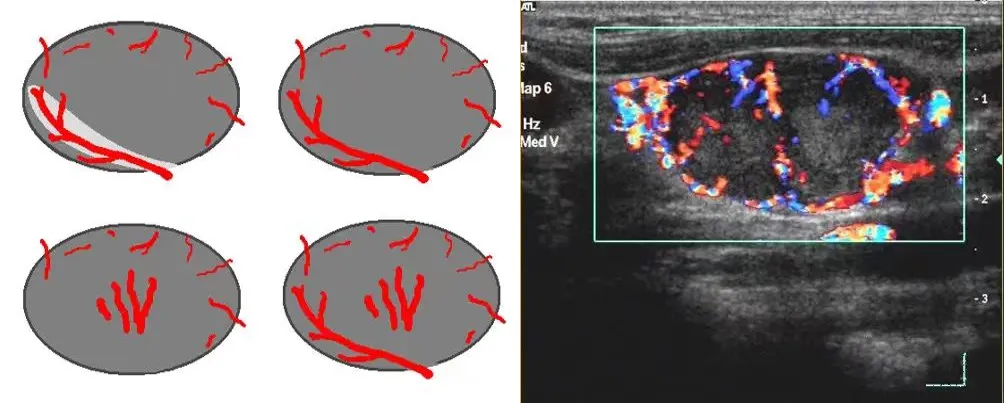

淋巴瘤

● 淋巴结不同程度肿大,多发,呈椭圆形、圆形,纵横比<2。

● 被膜清晰或不清晰,淋巴结之间可见融合。

● 皮质明显增厚呈低回声,不均匀,无液化、钙化;特征性回声改变为淋巴结内回声近似无回声的极低回声。

● 髓质变形或显示不清,或消失。

● 淋巴结内血流信号轻度或明显增多,分布杂乱;典型血流改变为淋巴结内血流信号丰富,红、蓝色血流信号充满整个淋巴结。

● 动脉血流速度加快,阻力指数正常或偏高。

淋巴瘤的血流信号在所有淋巴结中最为丰富。

淋巴结的内部回声一般表现为较均匀的低回声,当发生坏死时,其内部回声可相当低,接近无回声。